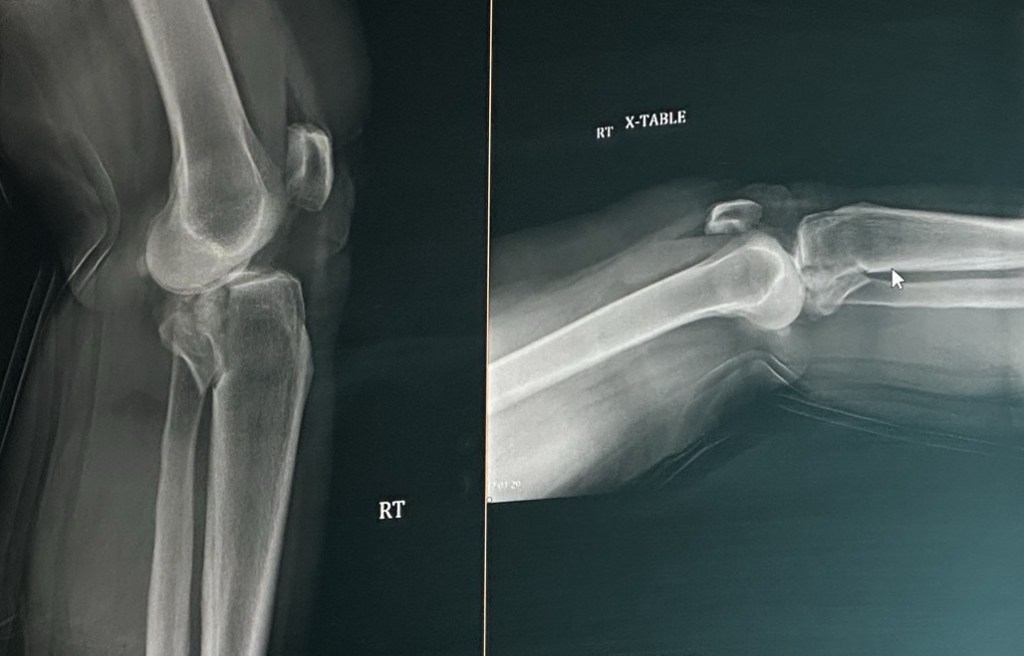

I admit, I haven’t been blogging in about four years but right now this is really the only thing I can do right now. Wednesday, I was painting my kitchen a beautiful teal color I was on the ladder, and the ladder started to slip, and I fell off the ladder and landed on my right leg. It was very painful. I screamed and thankfully Jillian heard me and called my neighbor. She did amazing, she was able to keep calm and take care of the dogs. I probably would have laid there until Jeff got home if she would not have been home since it was like 8:30 in the morning that would’ve been a long day in pain on the floor. I can’t thank my neighbors Vivian and Randy enough she came right over when Jillian called her. Randy followed shortly after he dropped their grandson off at school. They both were wonderful  I will be forever grateful to both of them for coming over so quickly. They called 911 and called work to let them know what happened and I wouldn’t be there for a while. I was taken to the hospital by ambulance. They did x-rays and two CT scans and determine that I broke my tibia plateau, which is part of the knee.

I had emergency surgery that night. I have a rod on either side of my leg and it’s just stabilized.